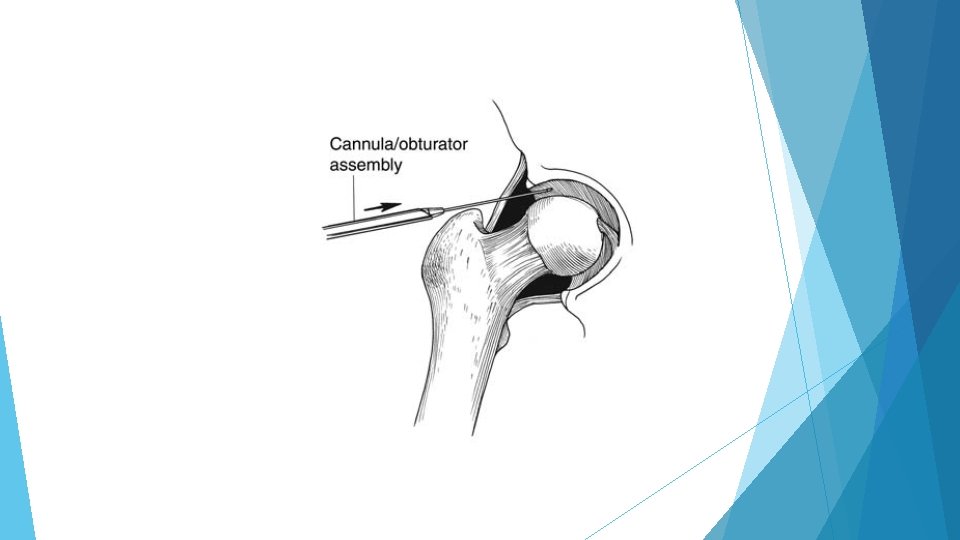

Hip Arthroscopy